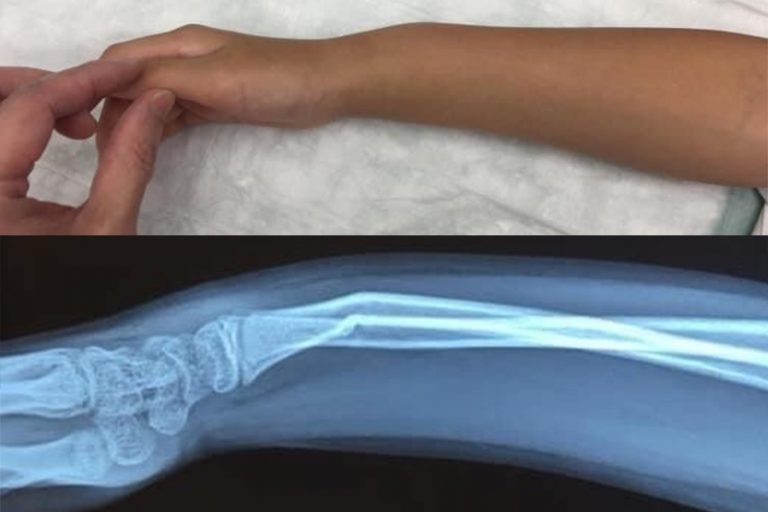

小童的骨質軟而有彈性,不用很大外力就能折彎,因此稍一不慎在耍樂蹦跳期間跌倒或從稍高位置跌下就有可能造成骨折。

常見會有外觀變形、彎曲的情況

醫生會先以X光去確定受傷位置和骨折的嚴重程度